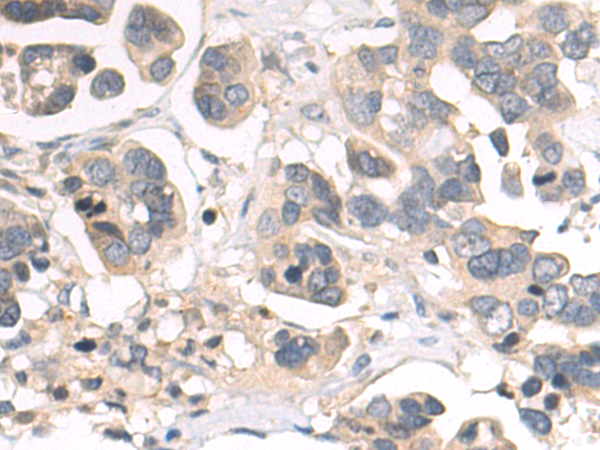

分类: 科研抗体货号: P06971别名: FETA, HPAFP应用: WB,IHC反应种属: Human